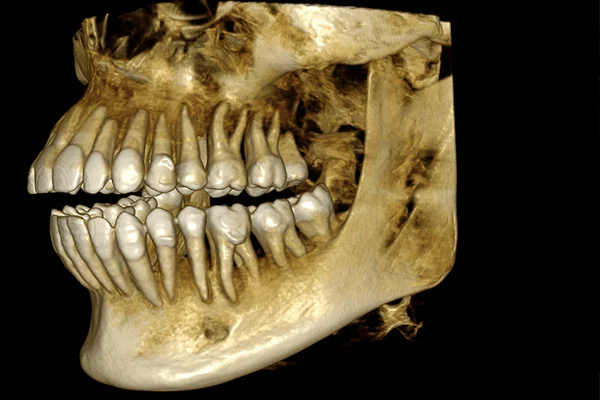

• 3D HD obraz s vysokým rozlišením 75 µm i pro velké objemy

• ANR pokročilá redukce šumu

• MAR patentované potlačení artefaktů s živým náhledem efektu filtru pomocí nezávislého algoritmu 3D (zcela unikátní)